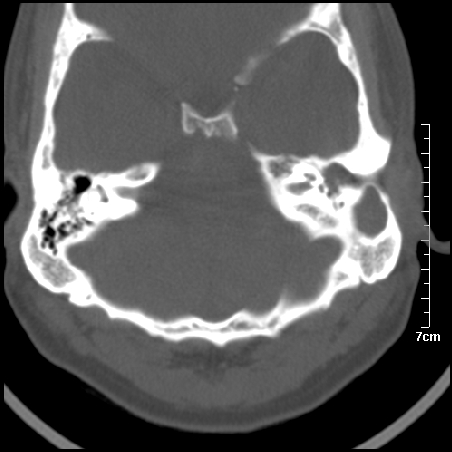

病例1

m/46y 头晕.耳鸣半月余 有乳突炎病史

病例2

m/27

胆脂瘤是是以鳞状上皮内衬充满角质化碎片的囊,随着角化屑片的不断堆积,肿块逐渐增大,胆脂瘤可为先天性(2%)或后天性(98%)。胆脂瘤有感染史。中耳内的鳞状上皮通常有外耳道的上皮通过一鼓膜的缺损移行至中耳,其他的原因包括鳞状上皮化生。由于欧氏管的功能不全所引起的中耳负压可产生上鼓室鼓膜松弛部的牵引性开袋。继而发展成胆脂瘤。成年人胆脂瘤时乳突常发育差,而儿童常有广泛性乳突气化,这种气化可导致胆脂瘤的更广泛的乳突扩散。后天性胆脂瘤患者大多数存在骨质破坏。

松弛部胆脂瘤有中央性穿孔或后上部牵引口袋所致。紧张部胆脂瘤经常侵蚀听小骨并引起传导性耳聋。

中耳胆脂瘤有两个重要并发症:一是面神经管的水平段受暴露,二是外侧半规管受侵蚀产生瘘管。面神经在ct上难以显示或不可能显示,除非其周围有空气包绕或有良好轮廓的骨性覆盖。胆脂瘤还可合并感染,产生于急性中耳炎.乳突炎所描述的那些合并症。